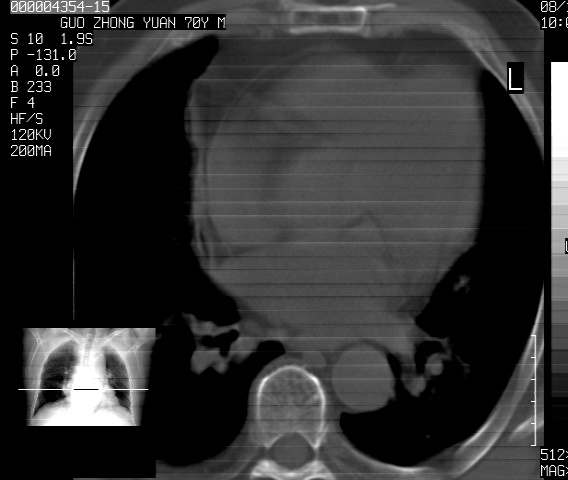

以下是引用sdzyy在2008-12-1 11:49:00的发言:[br]图像不全,请上传,右下肺炎症可能性大,占位待排.

以下是引用zjzjr在2008-12-1 14:53:00的发言:[br]图像不全,请上传,右下肺炎症可能性大,占位待排.心影增大,建议进一步检查.